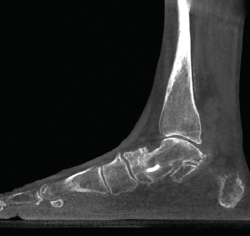

Lesiones de la sindesmosis

En la articulación tibioastragalina, la estabilidad de la articulación de la sindesmosis es un aspecto importante para evitar la aparición de lesiones articulares o artropatía progresiva.

En un contexto postraumático, la valoración de la afectación o la inestabilidad de la misma tiene su importancia para los resultados finales y los posibles tratamientos.

En la cuantificación del desplazamiento y de la inestabilidad de la sindesmosis es importante poder explorar la extremidad contralateral y la valoración en carga de los 2 tobillos.

Los estudios fisiológicos con TAC en carga muestran que el peroné presenta una rotación externa y un desplazamiento posterior con la carga(13).

La valoración inter- e intraobservador en lesiones traumáticas de la sindesmosis es mejor con la TAC en carga que con otros métodos diagnósticos(14,15).

Figura 7. Inestabilidad postraumática de la sindesmosis.

- Alteración-inestabilidad de la sindesmosis. Permite el estudio comparativo de la estabilidad de la sindesmosis (Figuras 7 y 8).